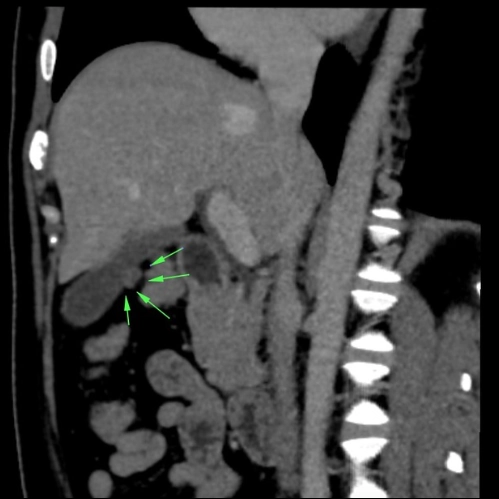

• Nang ống mật chủ (Choledochal Cyst)